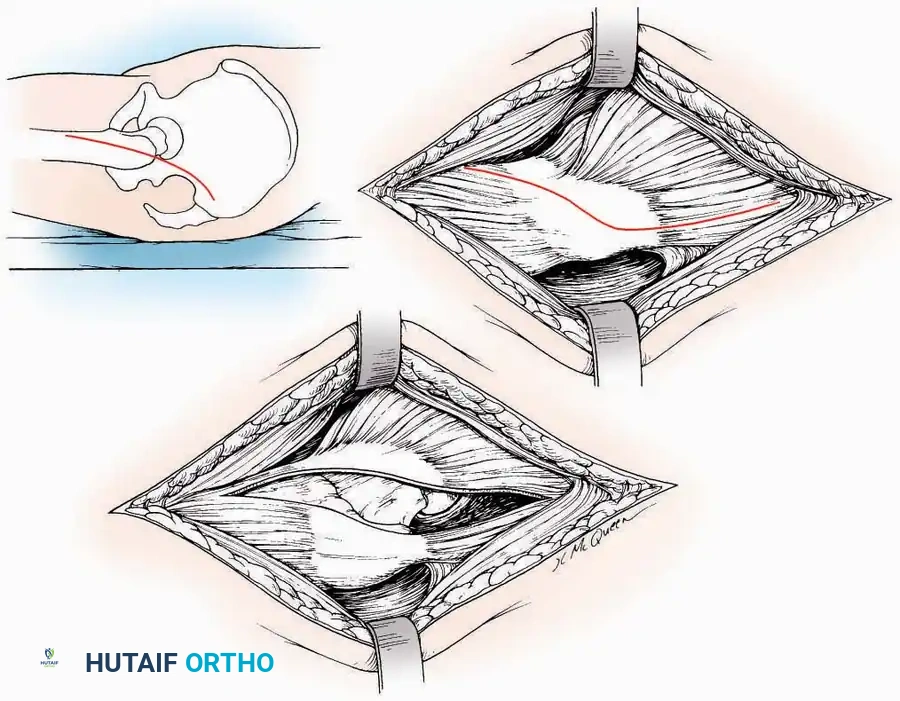

SURGICAL APPROACHES TO THE CALCANEUS

Approaches to the calcaneus are dictated by the pathology—trauma (intra-articular fractures) versus tumor/infection. Positioning is critical; while the prone position offers excellent bilateral access, the lateral decubitus or modified supine positions are more frequently utilized for unilateral trauma.

Lateral Approach (Extensile Lateral)

This is the workhorse approach for open reduction and internal fixation (ORIF) of displaced intra-articular calcaneal fractures.

Indications: ORIF of calcaneus fractures, lateral wall exostectomy, subtalar arthrodesis.

Positioning: Lateral decubitus with the operative leg up, or supine with a large bump under the ipsilateral hip to internally rotate the leg.

Surgical Technique:

* Incision: Begin the incision on the lateral margin of the Achilles tendon near its insertion. Extend it distally to a point 4 cm inferior and 2.5 cm anterior to the lateral malleolus. (For trauma, a classic L-shaped extensile incision is often used, dropping straight down anterior to the Achilles, then curving gently toward the base of the 5th metatarsal).

* Superficial Dissection: Divide the superficial and deep fasciae. It is imperative to create a "full-thickness" flap containing skin, subcutaneous fat, and periosteum to prevent flap necrosis.

* Nerve Protection: The sural nerve crosses the proximal and distal limbs of this approach. It must be identified and protected within the anterior flap.

* Deep Dissection: Isolate the peroneal tendons (longus and brevis). Incise and elevate the periosteum below the tendons to expose the lateral wall of the calcaneus.

* Tendon Management: If severe deformity or infection is present, the peroneal tendons may be divided via Z-plasty and repaired at the conclusion of the case, though this is rarely necessary in modern fracture care.